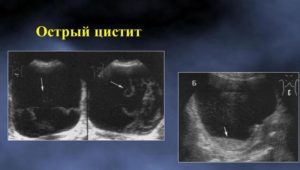

На эхо-картине пациента с острым циститом видны скопления клеток – эпителия, эритроцитов и лейкоцитов, которые в результатах исследования описываются термином «осадок». Если пациент лежит во время проведения УЗИ, то осадок локализуется около задней стенки пузыря. При вставании пациента осадок сместится к передней стенке.

При хронической форме патологии или при прогрессировании острого цистита результаты исследования покажут, что у органа неровный контур и стенки утолщены. Наличие кровяных сгустков в полости пузыря показывается на эхо-картине.

- При остром процессе сонография показывает признаки повышенной эхогенности, что свидетельствует о наличии воспалительных реакций. Осадок в моче пузырной полости выглядит в виде различных клеток и кристаллов солей. На начальном этапе развития цистита структура стенок органа остается ровной. Прогрессирование процесса вызывает развитие их ассиметричной формы.

- Хронический процесс при УЗИ отображается утолщением стенок мочевого пузыря и наличием осадочных хлопьев. При затяжном, хроническом течении процесса диагностируются наличие кровяных сгустков, прикрепленных к внутренним стенкам органа. На стадии процесса разжижения геморрагических сгустков их свертывание создает видимость неровных границ МП.